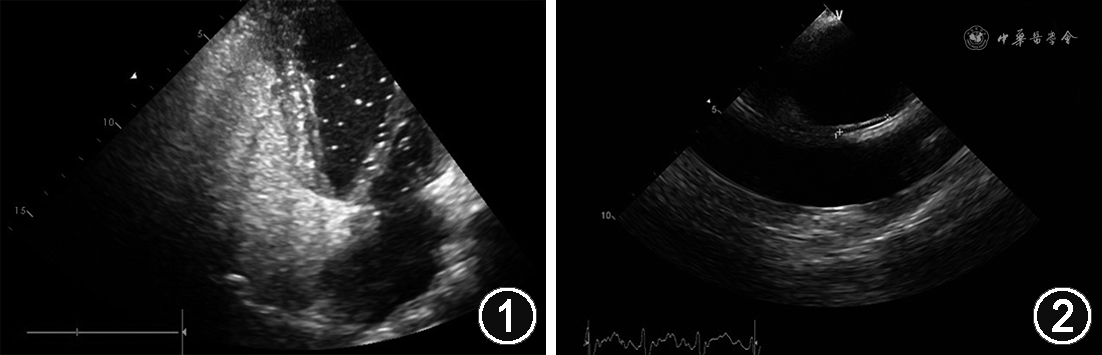

患者男,24岁,因“突发意识障碍伴肢体抽搐1个月”于2020年3月5日入院,患者1个月前在跑步训练后突发意识障碍、呼之不应,伴有肢体强制性抽搐,就诊于联勤保障部队928医院,头颅MRI、脑血管成像及脑电图检查均未见异常。既往无高血压、糖尿病、吸烟、卒中或短暂性脑缺血发作、皮层梗死病史。住院期间仍有上述症状发作,行精神心理评估未见异常,建议转上级医院治疗。入院查体:血压118/76 mmHg(1 mmHg=0.133 kPa),双肺呼吸音清,未闻及干湿性啰音。心率68次/min,律齐,各瓣膜听诊区未闻及病理性杂音,腹部平软,无压痛及反跳痛,双下肢及眼睑无水肿。该患者反常栓塞风险量表(RoPE)评分为10分,高度提示卵圆孔未闭(patent foramen ovale,PFO)。2020年3月7日在我院行经胸超声心动图(TTE)示房间隔中部柔软、菲薄,右心声学造影检查提示心房水平中大量右向左分流(right to left shunt,RLS)(图1),经食道超声心动图(TEE)显示PFO属于长隧道型,测量PFO大小约1.5 mm,长度约16.7 mm(图2)。